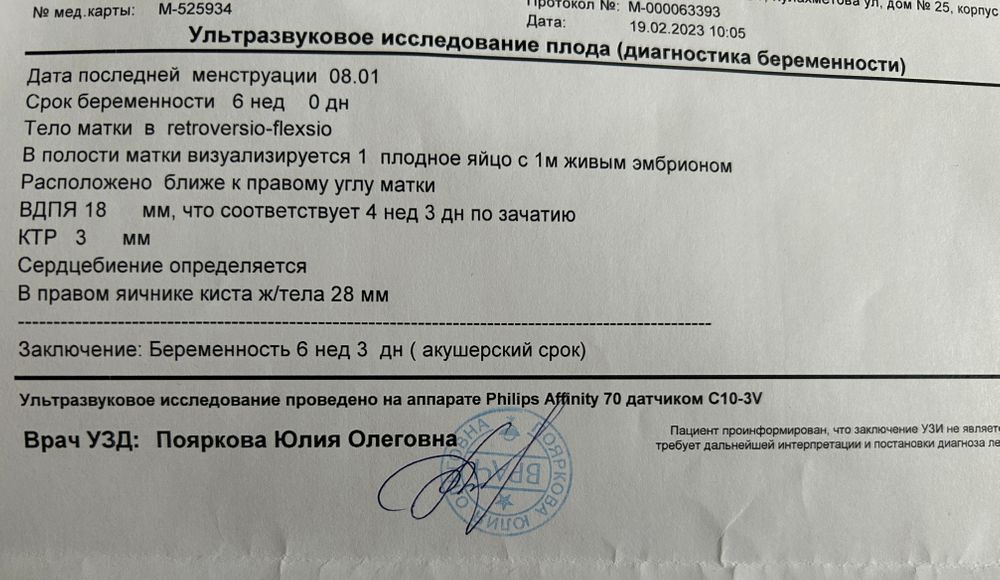

Сходила на я на узи и вроде бы все хорошо ☺️и сердцебиение определяется🙏🏻 И надо мне уже расслабиться и просто наслаждаться очень желанной беременностью🤰🏼Но…

Меня смущает разница между плодным яйцом и ктр. Само плодное яйцо опережает мой срок, ктр в рамки вроде вписывается.

Ну и конечно же снова со мной киста желтого тела. Она была и при замершей беременности со мной.

Как же хорошо, что следующие узи ровно через неделю уже в жк🥳 При положительном узи в этот же день гиня меня поставит на учет🙏🏻